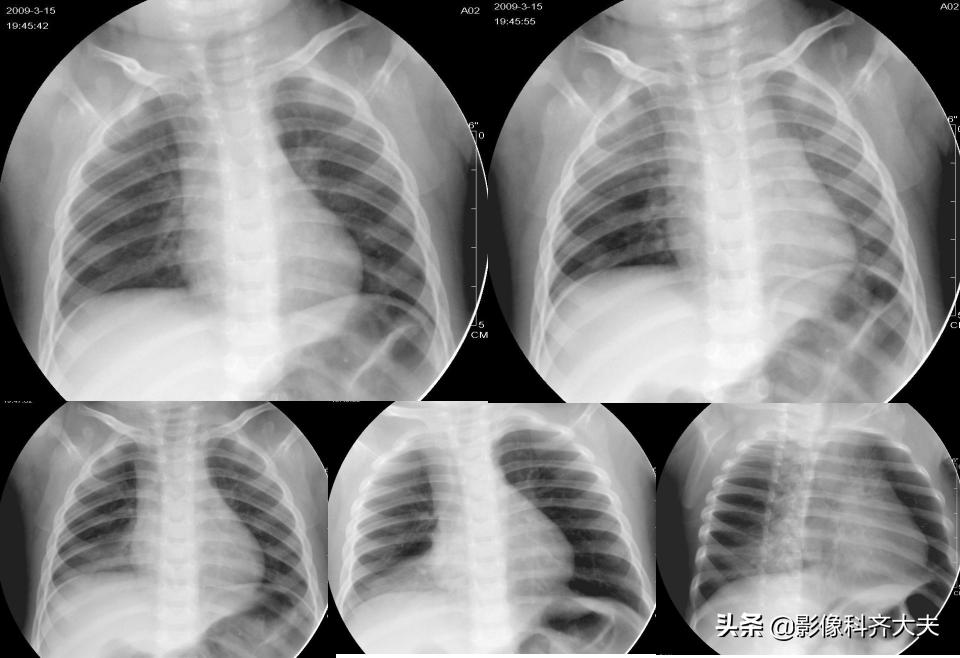

病例1、病史:女1岁6月,3天前有异物呛入史。

图1 图2

图1及图2左肺均有肺气肿表现;图1为吸气像纵隔居中,图2为呼气相纵隔向右侧(健侧)移位,即:纵隔摆动。提示左侧支气管有异物存在的可能。

病例2、病史:患儿,女,一岁半,吃花生米出现呛咳一小时入院,临床初步诊断“气管异物”

胸部透视图

胸部透视发现左肺有肺气肿表现,吸气像纵隔居中,呼气后纵隔右移,即:纵隔摆动;连续变换体位发现右肺下野有片状高密度影,提示有肺不张或肺炎的可能。综上提示右肺下叶支气管可能存在异物。

病例3、病史:患儿,1岁,近日出现咳喘,不缓解。无明确异物吸入史。3

图3 图4

图3及图4左肺均有肺气肿表现;图3为吸气像纵隔居中,图4为呼气相纵隔向右侧移位,即:纵隔摆动。提示左侧支气管有异物存在的可能。

X线检查:纵隔摆动

任何原因导致的气道阻塞均可造成两侧胸内压力差增大,可出现纵隔摆动现象,然而体征在气管支气管异物患者中出现率低于40%;患儿哭闹、不配合检查,很难掌握其呼吸气象,分别摄吸气像和呼气的成功率很低。

综上,出现漏诊的概率极高。即使确诊,也不能将异物存在的具体部位直接显示。